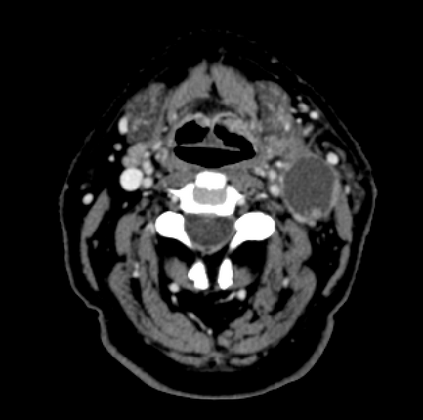

Organ at risk (OAR) segmentation is a critical process in radiotherapy treatment planning such as head and neck tumors. Nevertheless, in clinical practice, radiation oncologists predominantly perform OAR segmentations manually on CT scans. This manual process is highly time-consuming and expensive, limiting the number of patients who can receive timely radiotherapy. Additionally, CT scans offer lower soft-tissue contrast compared to MRI. Despite MRI providing superior soft-tissue visualization, its time-consuming nature makes it infeasible for real-time treatment planning. To address these challenges, we propose a method called SegReg, which utilizes Elastic Symmetric Normalization for registering MRI to perform OAR segmentation. SegReg outperforms the CT-only baseline by 16.78% in mDSC and 18.77% in mIoU, showing that it effectively combines the geometric accuracy of CT with the superior soft-tissue contrast of MRI, making accurate automated OAR segmentation for clinical practice become possible. See project website https://steve-zeyu-zhang.github.io/SegReg